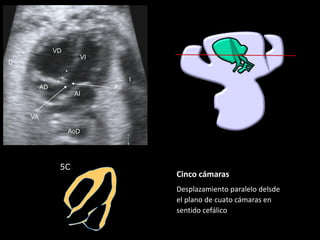

5C

Cinco cámaras

Desplazamiento paralelo delsde

el plano de cuato cámaras en

sentido cefálico

VI

VD

Ao

VA

AoD

AD

▪ Ao sale de VI

▪ Se continúa con el

septo IV